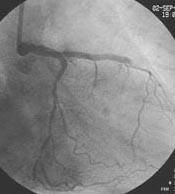

Fig2 2本のBMWをまず入れて、LMT-LADを2.0mmで前拡張しました。これは、自分的に

は非常にTipsと思っている手技で、これをやることで、IVUS中も、Flexicutの位置決

めの際も、antegrade flowがまず得られますから、hemodynamic collapseを回避で

き、ゆっくり余裕をもって手技を行うことができます。また、こうした病変のplaque

は大抵LCxの対側が中心ですから、いくらLCx入口部方向からカットするといっても

結局LCx入口部方向には、もっともFlexicutのバルーンが高圧であたることになりま

す。バルーンに対するLCx入口部の反応性も予測できます。もし、2.0mmのバルーン

でこちらがdelayになるくらいなら、LCx方向へのワイヤを抜いてDCAなんていう手技

はつらいと思います。万一、2.0mmのバルーンでLCxがダメになりそうなら、DCAはあ

きらめて、kissing stentで逃げてくるつもりでした。LMTは2連銃になるのは仕方な

いと思いました。いざというとき、kissing stentも可能という意味で、こうした病

変では8Frガイドが必須と思います。

Fig.2

Fig3 2.0mmで拡張後です。幸い、LCx入口部は大丈夫でした。